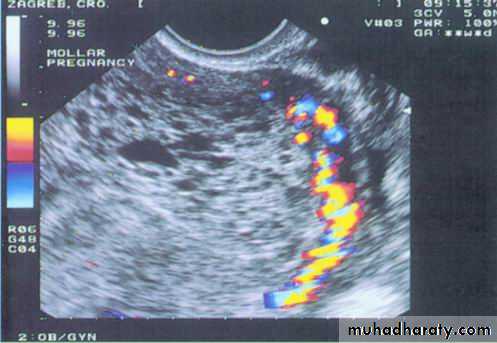

Color Doppler image of a hydatidiform mole and surrounding vessels. The uterine artery is easily identified from its anatomical location.The clues for the sonographer in this diagnosis are the presence of a fetus (although usually with severe, but nonspecific, abnormalities) in combination with a formed placenta containing numerous cystic spaces

Partial Hydatidiform Mole

Partial hydartidiform mole